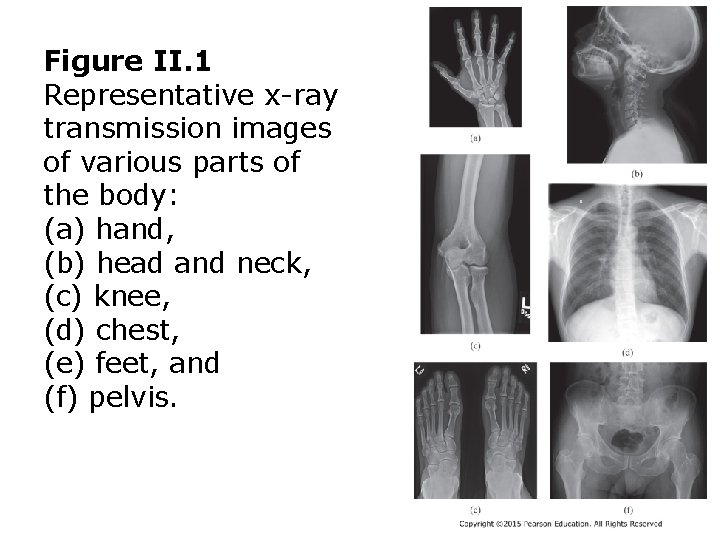

Figure II. 1 Representative x-ray transmission images of various parts of the body: (a) hand, (b) head and neck, (c) knee, (d) chest, (e) feet, and (f) pelvis.